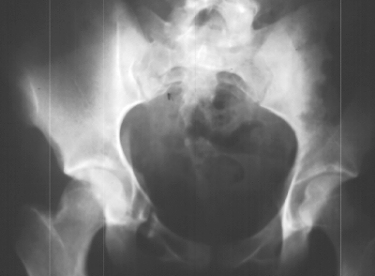

A 16 year old female was previously in good health when she was involved in a roll-over motor vehicle accident as an unrestrained passenger, and ejected from the vehicle. She landed in a field. She was taken by ambulance to a nearby hospital complaining of pain in the pelvis. An x-ray of her pelvis was obtained (image 1), Obturator and iliac oblique(image 2), A CT scan of the fracture was obtained (images 3, 4 & 5).